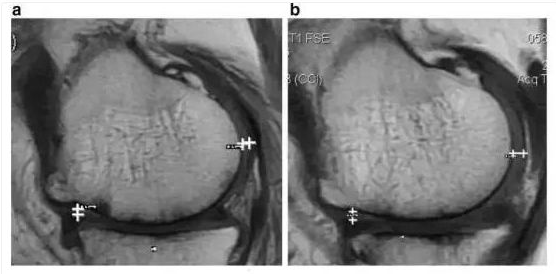

对10例患者关节腔内注射脐带来源干细胞和PRP,治疗后2年检测结果,WOMAC评分也得到改善,60%的病人的软骨体积增加。

治疗后(b)比治疗前(a)的软骨厚度增加

注:两条白色长度表示厚度